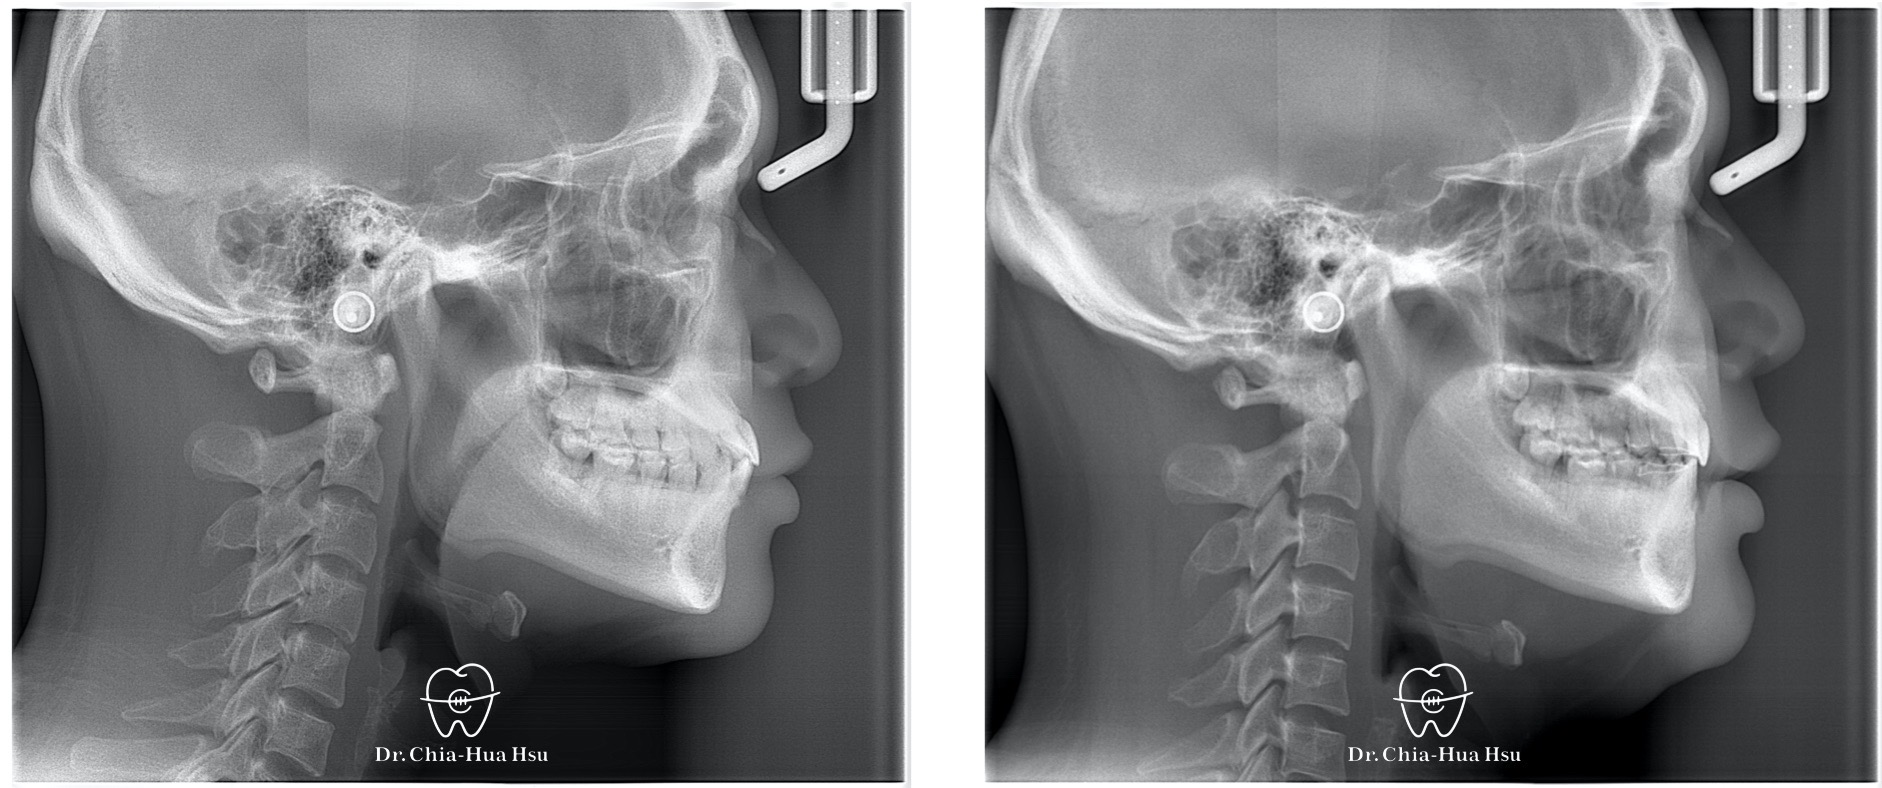

治療前

治療後